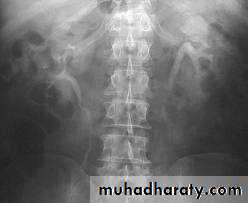

-Over 90% of calculi are radiopaque on plain films and virtually all on CT as very sensitive for detection of calculi, even those that appear radiolucent on plain film.

-Plain film may be useful in demonstrating calculi.